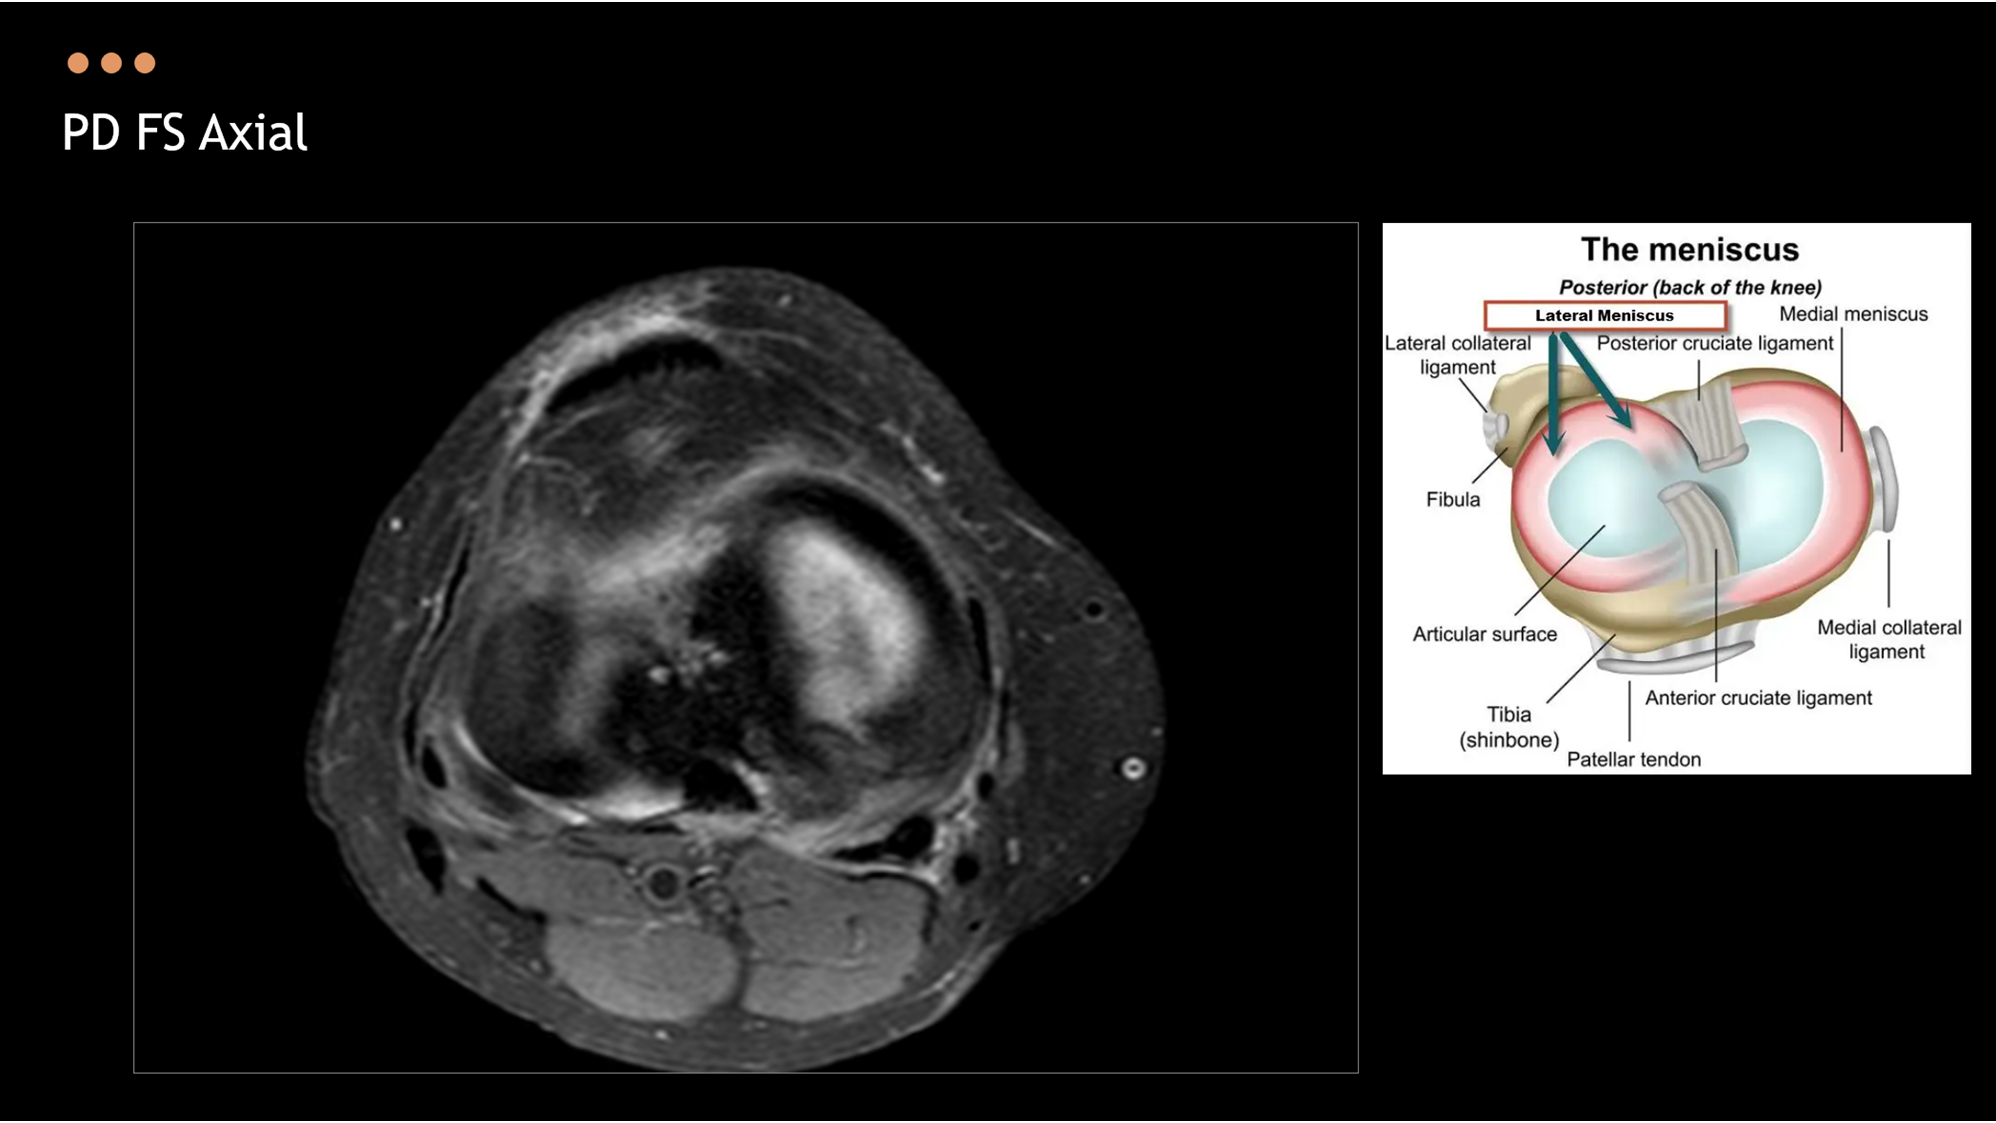

2025 Spring Meeting 한의영상 최신지견